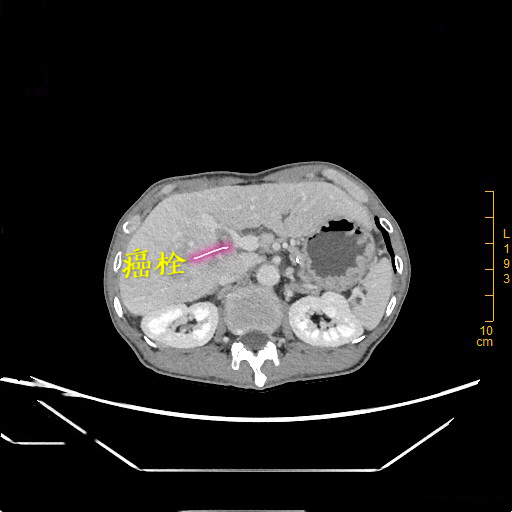

患者为65岁的老年男性,无意中发现右上腹有一个鸡蛋大小包块,偶尔会有胀痛,未予以重视,肿块进行性长大,检查提示肝脏肿物,遂到深大总院肝胆外科就诊。李晓武教授及其团队接诊后,发现患者较为消瘦,身高176cm却仅有43kg的体重,经查体发现患者包块巨大,下缘已达盆腔位置,极为罕见。进一步CT检查结果显示,患者的肿瘤已占据肝脏右叶大部分,直径达13cm,向后压迫下腔静脉,向下压迫结肠等肠管,并且伴有门静脉右支癌栓及右肝静脉癌栓形成。

李晓武 教授团队仔细阅读影像片后指出:肝脏恶性肿瘤手术既要保证肿瘤的根治切除,又需要保证手术切除后肝脏功能满足人体需要,手术、麻醉、术中出血、术后感染等对肝脏功能均有影响,此例患者肿瘤巨大,单是切除肿瘤已有很大难度;肿瘤与血管关系密切,术中出血也是个难题;切除后肝脏功能维持更是难点。需要术中精准切除、减少出血、尽量保留有功能肝脏及其功能血管,难度巨大。